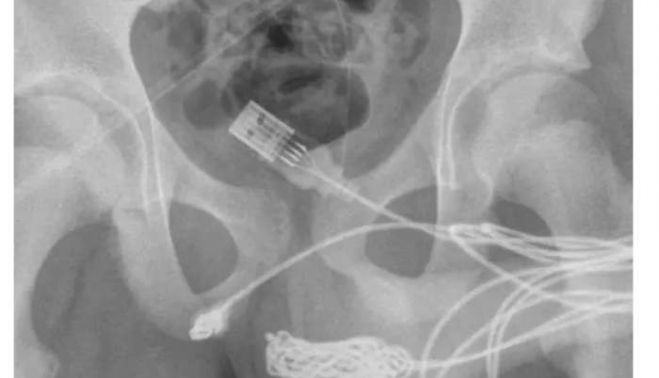

“Se descubrió que los dos puertos distales del cable USB sobresalían del meato uretral externo, mientras que la parte media del cable anudado permanecía dentro de la uretra”, indicaron los médicos en un informe difundido por ScienceDirect.com.

En un primer momento, los expertos buscaron extraer el cable del pene con una varilla de metal. Pero como había una gran cantidad de nudos en el cable, el paciente tuvo que ser operado.